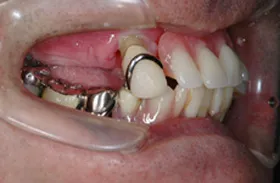

インプラント治療及び補綴治療のケース

■治療前:奥歯が無いため噛み合わせが深く下の歯が全く見えない

噛み合わせが低いため全体的に歯が削れている

■治療後:下顎 左下5・6番、右下4・6番にインプラント治療

その他の歯に補綴治療をしたことにより、奥歯もしっかりと咬むことができ、奥歯ができたことにより噛み合わせも上がって下の歯も見えるようになり、審美的にも改善された

| 主訴 | 歯科治療をしても歯がすぐに欠けてしまう 奥歯が無いため、奥歯で咬めない |

| 治療方法 | インプラント治療 + 補綴治療 |

| 治療期間 | 約1年 |

| 通院回数等 | 約20回 |

| 費用 | 約250万円(税込) |

| リスク・副作用 | 術後の腫れ・痛み |